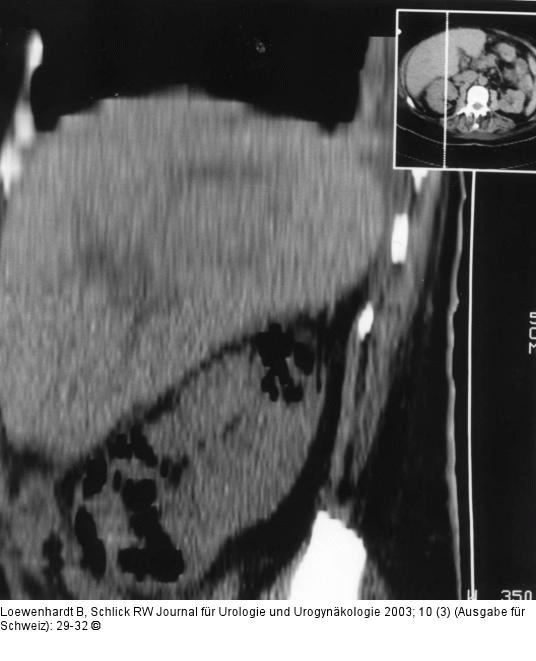

Abbildung 1: Emphysematöse Pyelonephritis In der rechtsparamedianen sagittalen Rekonstruktion kommt die diffuse Gasdurchsetzung der Niere in nahezu der gesamten Ausdehnung zur Darstellung, wobei die Polbereiche bevorzugt sind. |

Abbildung 1: Emphysematöse Pyelonephritis

In der rechtsparamedianen sagittalen Rekonstruktion kommt die diffuse Gasdurchsetzung der Niere in nahezu der gesamten Ausdehnung zur Darstellung, wobei die Polbereiche bevorzugt sind. |